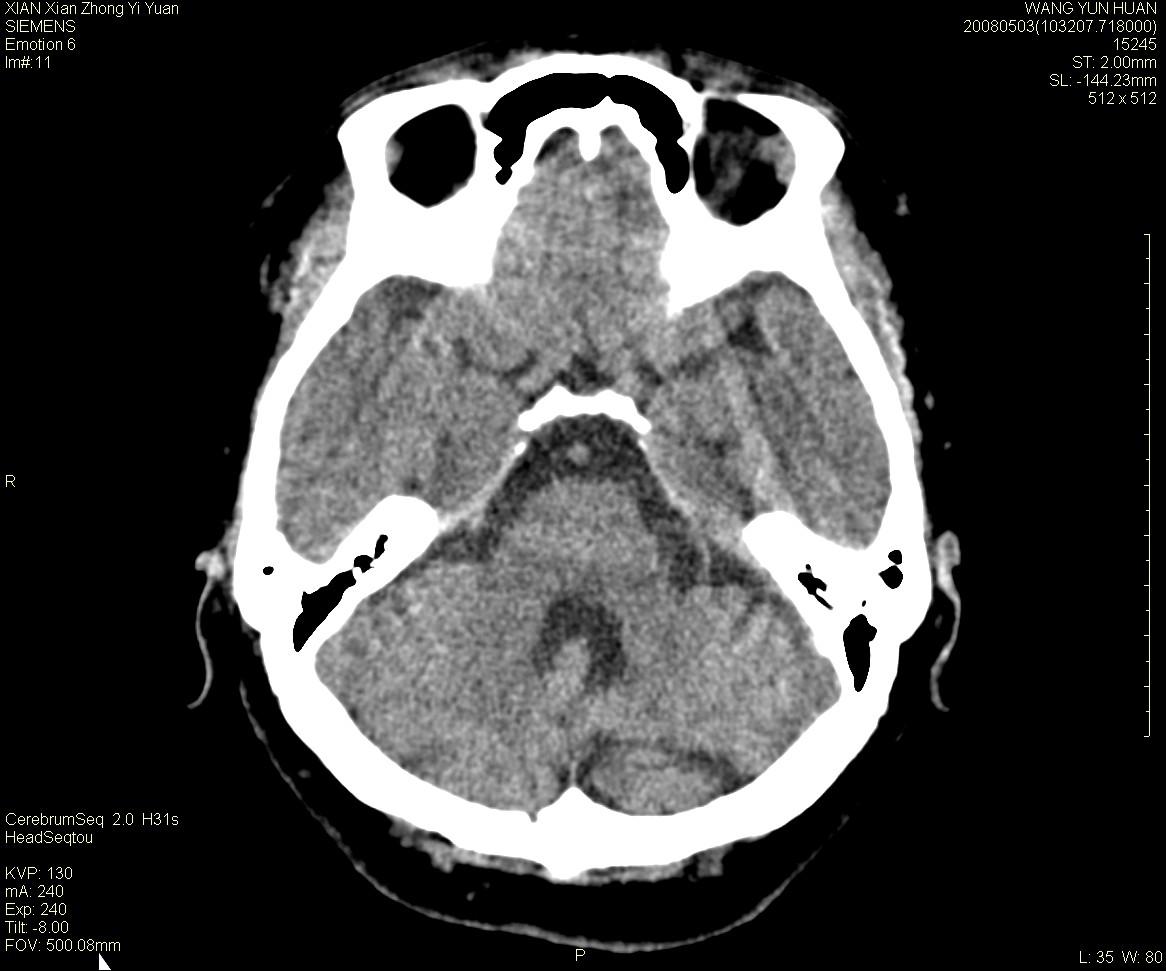

标题: CT13219:(补充强化)请会诊,患者女,60岁,头晕,大家看 [打印本页]

标题: CT13219:(补充强化)请会诊,患者女,60岁,头晕,大家看

病灶显示轻度强化,ct增加4hu左右,大家看是什么肿瘤.

小脑蚓部占位,考虑脑膜瘤。增强吧

小脑蚓部囊型肿块,内有实性结节及钙化点。增强后囊壁及结节轻度强化。

考虑蚓部星形细胞瘤(ⅱ级可能性大)。

小脑蚓部肿块,周围无明显占位效应及水肿带,增强轻度强化,考虑低分级星形细胞瘤。